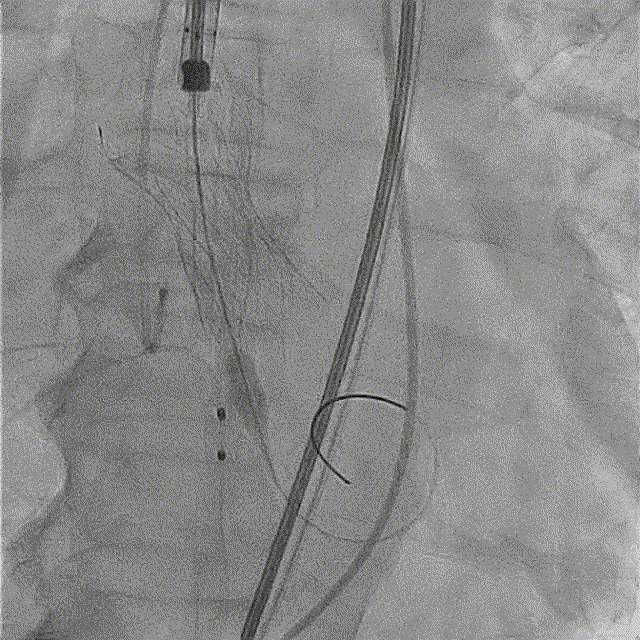

全麻后超声引导下建立入路,左侧股动脉置入TaurusNavi 20F血管鞘。跨瓣后左室放置Lunderquist导丝,使用TaurusAtlas 20mm球囊预扩,球囊无明显位移,有轻微腰征、无漏。输送系统预备同侧Snare从右股动脉送入,安全顺利通过主动脉弓。瓣膜在双窦展开位约瓣上2mm位初始定位释放,工作位造影多角度评估后予以释放(一次定位释放,未采用多次回收功能)。超声下显示瓣膜偏椭圆,之后使用TaurusAtlas 22mm球囊后扩,支架形态改善明显,导管测压由术前的70mmHg即刻下降至1mmHg,术后即刻超声心动图评估显示瓣膜位置良好,微量瓣周漏,血流动力学指标理想。

瓣膜初始定位

工作位造影(双窦展开位)